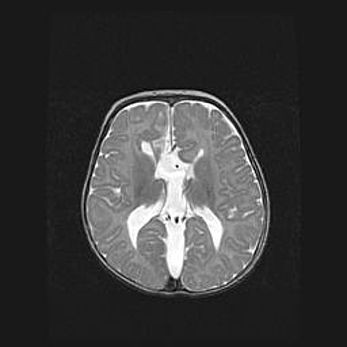

Церебральная ишемия II.

Возраст: 5 дней

Вес: 3400 г

Пол: женский

Окружность головы: 35 см

Срок гестации: 39 недель

Церебральная ишемия – это заболевание, характеризующееся недостаточностью (гипоксией) либо полным прекращением (аноксией) снабжения мозга кислородом по причине закупорки одного или нескольких сосудов. Это приводит к  что метаболическим расстройствам различной степени тяжести в тканях головного мозга, развитию коагуляционных некрозов и гибели нейронов.